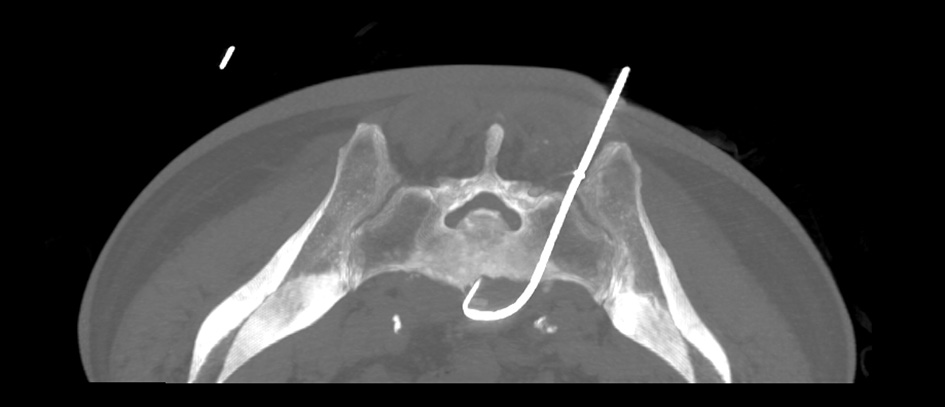

After the needle had penetrated the sacrum, stylet was removed and presence of pus flow was detected. A guide wire was passed through the bone marrow biopsy needle into the abscess cavity. After confirming with CT fluoroscopy that guide wire is in the correct place, bone marrow needle was removed. A 8 Fr locking pigtail catheter (Cook medical) was passed over the guide wire into the cavity. Finally, the guide wire was removed leaving the catheter within the abscess cavity (Fig. 3).

After the catheter placement approximately 60 ml of puss was aspirated. Neither early nor late procedure-related complications like bleeding, nerve injury, bone fracture, osteomyelitis or bone abscess occurred. Sixteen days after drainage procedure, the catheter was withdrawn as patient’s condition improved, the outflow of pus had reduced considerably and inflammatory blood signs were back to normal.